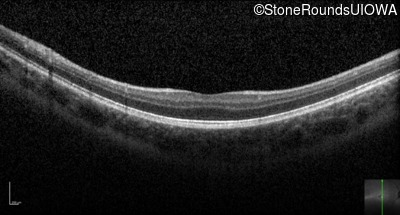

Optical Coherence Tomography - Right - 20/63 -1 sc

Exemplar / OCT Stack

OCT Stack